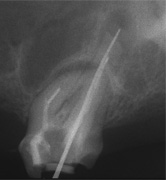

Wurzelkanalbehandlung und Resektion wurden innerhalb eines Monats abgearbeitet und sind hier erwähnenswert auch nur vielleicht, weil von Natur aus lange Eckzahnwurzeln intra operationem subjektiv endlos lang werden können und weil hier

der Behandlungserfolg 10 Jahre nach dem Eingriff durch eine neue Aufnahme belegt werden kann. Wie alle anderen Aufnahmen auch,

1 und 2 sind von 2000, die 3. ist vom 10.06.2010